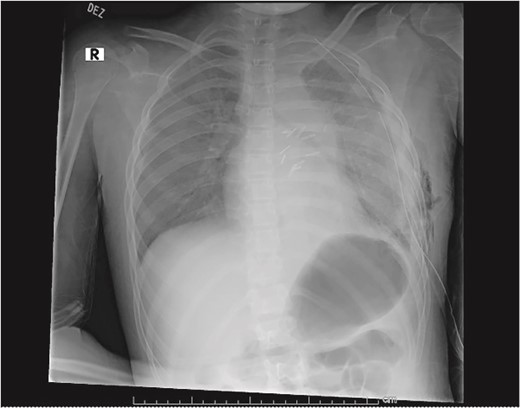

Our patient is a 10-year-old Caucasian female with a history of early adrenarche, ADHD, and COVID-19 and no past surgical history. She presented to the ED with a month-long history of persistent coughing, shortness of breath on exertion and speaking, and left-sided chest pain that began after a diagnosis of mildly symptomatic COVID-19. A physical exam revealed decreased breath sounds on the left, with a left-sided chest protrusion. A plain film and CT demonstrated a normal right lung, with a significant mediastinal shift toward the right, displacement of the heart into the right hemithorax, with complete whiteout of the left hemithorax, and demonstrating a mix of solid and cystic foci, with a round opacification at the left lung base (Figs 1 and 2). The patient underwent an uncomplicated left thoracotomy with excision of two masses, one being 22.5 × 21.0 × 10.5 cm and the other being 13.5 × 11.5 × 6.2 cm. These masses weighed 2394 g in aggregate. The specimens consisted of well-encapsulated tumors attached to the posterior aspect of the chest wall. A regional, positive lymph node measuring 3.0 × 2.2 × 1.0 cm was also resected. Due to the large size of the tumor and the requirement for clean margins, parts of the latissimus dorsi and serratus anterior muscles were also resected. By postoperative day (POD) 0, the left lung had already filled the left hemithorax, and the mediastinal shift had corrected (Fig. 3). The chest tube was removed on POD 5, and a plain film showed continued expansion of the lung to full size and resolving pulmonary edema and atelectasis (Fig. 4). The patient was discharged home on POD 5. The tumor staging was T4N1M0. The tumor was positive for vimentin, CD56, synaptophysin, chromogranin, and NSE. The tumor was negative for pancytokeratin, Cam5.2, EMA, S100, desmin, SMA, SOX10, HMB45, CD117, DOG1, CD99, PR, CD68, WT1, CD30, p53, Alk1, GFAP, and nuclear β-catenin. Next-generation sequencing showed an MGA:NUTM1 fusion, supporting a final diagnosis of high-grade MGA:NUTM1 fusion SCS. Given the size and grading of the tumor, the patient underwent adjuvant CT-RT with ifosfamide, doxorubicin, and proton beam radiotherapy, with supportive doses of MESNA and dexrazoxane for 4.5 months post-operatively. The basis of this treatment is ARST0332 Arm C [6]. Before treatment initiation, the patient underwent an uncomplicated left oophorectomy for reproductive cryopreservation. A PET/CT prior to CT-RT showed hypermetabolic activity in several areas. These included the pleural resection margin, a mediastinal lymph node concerning for metastasis versus postsurgical change, and a left axillary lymph node concerning for metastatic disease. During treatment, the patient contracted human metapneumovirus and rhino/enterovirus, resulting in febrile neutropenia. The patient was successfully treated with blood and platelet transfusions and pegfilgrastim. Upon completion of CT-RT, PET/CT imaging showed no evidence of residual disease, with minimal focal hypermetabolic activity as compared to the previous imaging (Fig. 5).

Plain film on postoperative day 0 depicting the recovery of the left lung post-surgical resection.